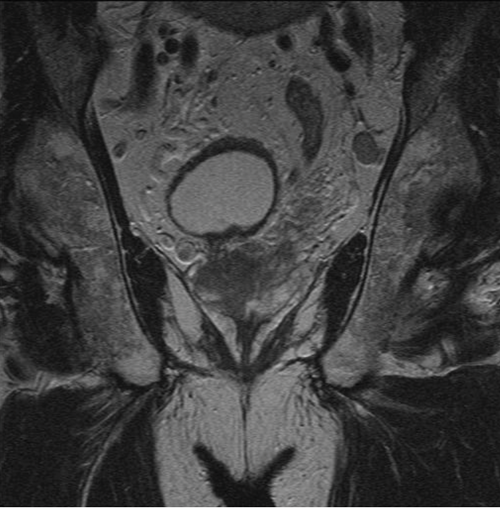

A 70-year-old male presented with a prostate specific antigen (PSA) of 5.2 and had MRI of the prostate.

1. What sequence and plane is the MRI image?

2. Describe the findings.

3. What is the radiological staging from the image shown?

- Coronal, T2-weighted MRI. Fluid is bright on T2 and dark on T1 MRI. The bladder can clearly be seen on this image and is bright.

- Low signal is seen predominantly in the right lobe of the prostate and there is bulging of the capsule. Seminal vesicles are not clearly seen on this image so it is difficult to comment on whether they are involved. There is a round, enlarged lymph node in the left hemi-pelvis.

- Radiological staging from this image alone is T3a, N1, M0. There is bulging of the capsule and extracapsular disease, and the left pelvic lymph node has typical appearance of a metastatic node. There is no fatty hilum, it is enlarged and is rounded rather than ovoid. Bone involvement is difficult to accurately assess on T2 MRI and T1 images should be evaluated to assess the pelvic bones and lower lumbar spine.